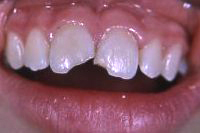

Ein 9-jähriges Mädchen kam eine Stunde nach einem Sturz, bei welchem es den linken oberen mittleren Schneidezahn komplett herausgeschlagen und den rechten massiv traumatisiert hatte (wackelte sehr stark), in unser Praxis (Röntgenbild Abb. 3). Der herausgeschlagene Zahn wurde sofort replantiert und beide mittleren Schneidezähne in die ursprüngliche Lage zurückversetzt und in dieser Situation mittels eines Drahtbogens an die Nachbarzähne fixiert (Röntgenbild Abb. 4).

Die verletzten Schneidezähne mussten beide wurzelbehandelt werden (Röntgenbild Abb. 5, siehe auch Kapitel Endodontie).

Einen Monat später haben wir beide Zähne intern gebleicht und dann die abgebrochenen Zähne wieder aufgebaut (Abb. 6 und 7).